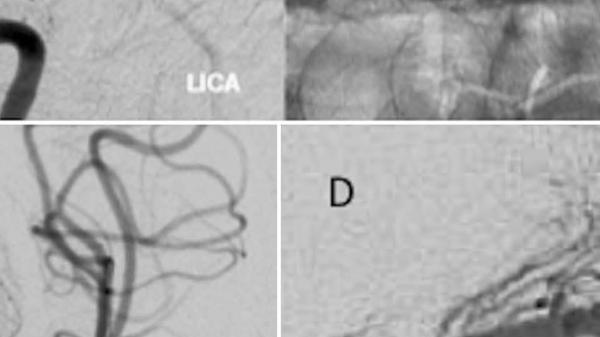

Στενώσεις ενδοκράνιων αγγείων – Ενδείξεις αντιμετώπισης

• Στενώσεις ενδοκράνιων αγγείων – Ενδείξεις αντιμετώπισης